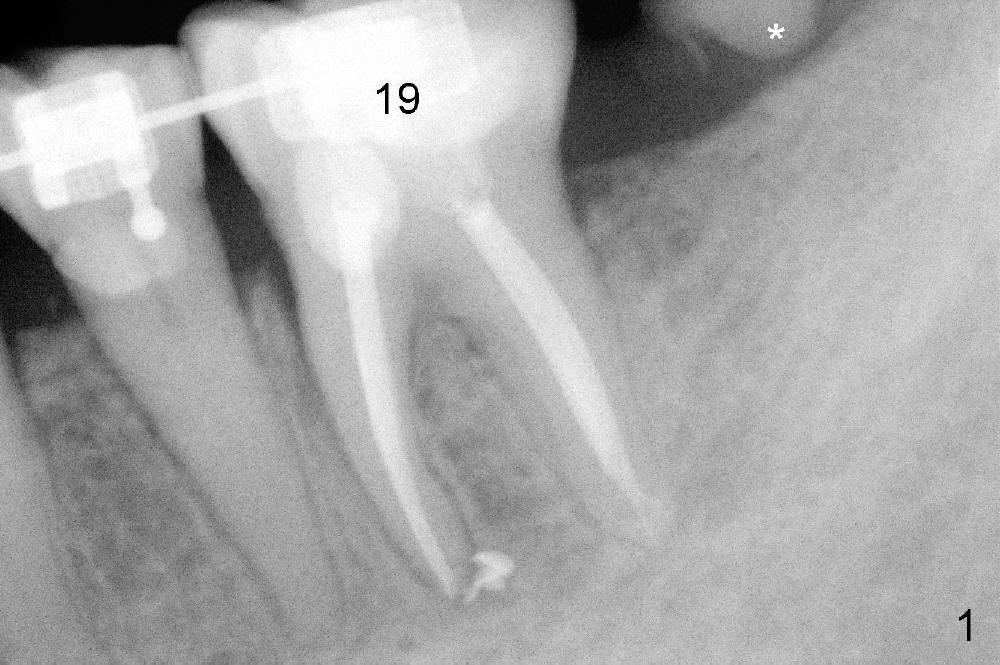

Planning gives the surgery and assistants confidence. Implant placement seems to be more smoothly. A preop PA (Fig.1) shows that the periapical radiolucency of the neighboring tooth #19 disappears. Removal of the residual roots of the teeth #17 and 18 (Fig.1 *) gives rise to a nice surgical field (Fig.2, the sockets packed with Clindamycin soaked gauze). Immediate implant osteotomy is formed as mesial as possible of the wound. Attention is being paid to buccolingual trajectory when the first pilot drill is used (not shown). An intraop PA is taken with a 3.8 mm tap in place to confirm the depth of the osteotomy relative to the inferior alveolar canal (Fig.3). A 4.5x12 mm implant is placed as planned (Fig.4). The elongated wound (mesiodistally) allows the wound to approximate around the implant/healing abutment with sutures (Fig.5). The gingiva heals 8 days postop (Fig.6). The 1st 4 coronal threads remains outside the bone 3.5 months postop (Fig.7 >). It appears that less thread exposure 1 year 7 months postop (Fig.8), suggesting bone growth. To prevent periimplantitis and facilitate restoration, place 2nd molar implant as deep as possible with slightly shorter implant.